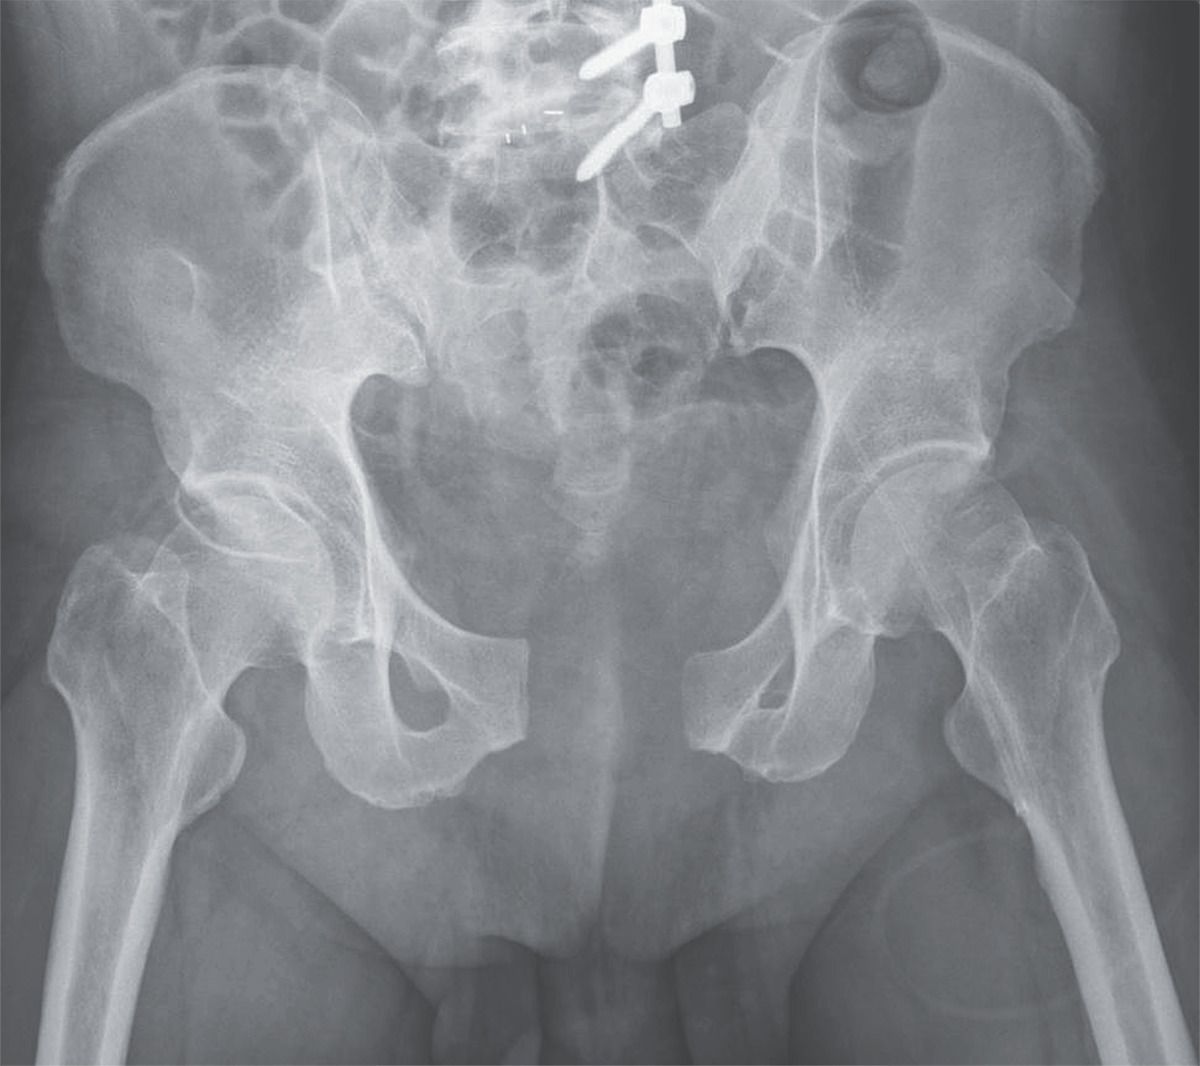

A 45-year-old man was brought to the emergency department after a motorcycle accident. He had a history of low back pain and disk herniation and had undergone transforaminal lumbar interbody fusion of the L5 to S1 vertebrae 5 years earlier. The physical examination was notable for a bruise in the pubic area, and manual compression elicited severe pain in the anterior and posterior pelvic areas, findings consistent with an unstable pelvis. Circumferential pelvic sheeting was applied to stabilize the pelvic ring. A radiograph of the pelvis showed a widening of the pubic symphysis of more than 5 cm. Also known as an open-book fracture, this injury typically occurs after high-energy blunt trauma, such as that caused in a motorcycle accident or by a fall from height. Such injuries may cause extensive bleeding and neurologic damage and may be associated with urogenital injuries. To restore the stability of the posterior pelvic rim, a Pfannenstiel approach was used for internal plate fixation, augmented with a supra-acetabular external skeletal fixator for the anterior rim and a percutaneous sacroiliac screw for fixation of the left posterior rim. The patient was able to sustain partial weight bearing with crutches after the surgery and participated in rehabilitation. Within 2 months after surgery, the external fixator was removed, and he was able to bear his full weight.